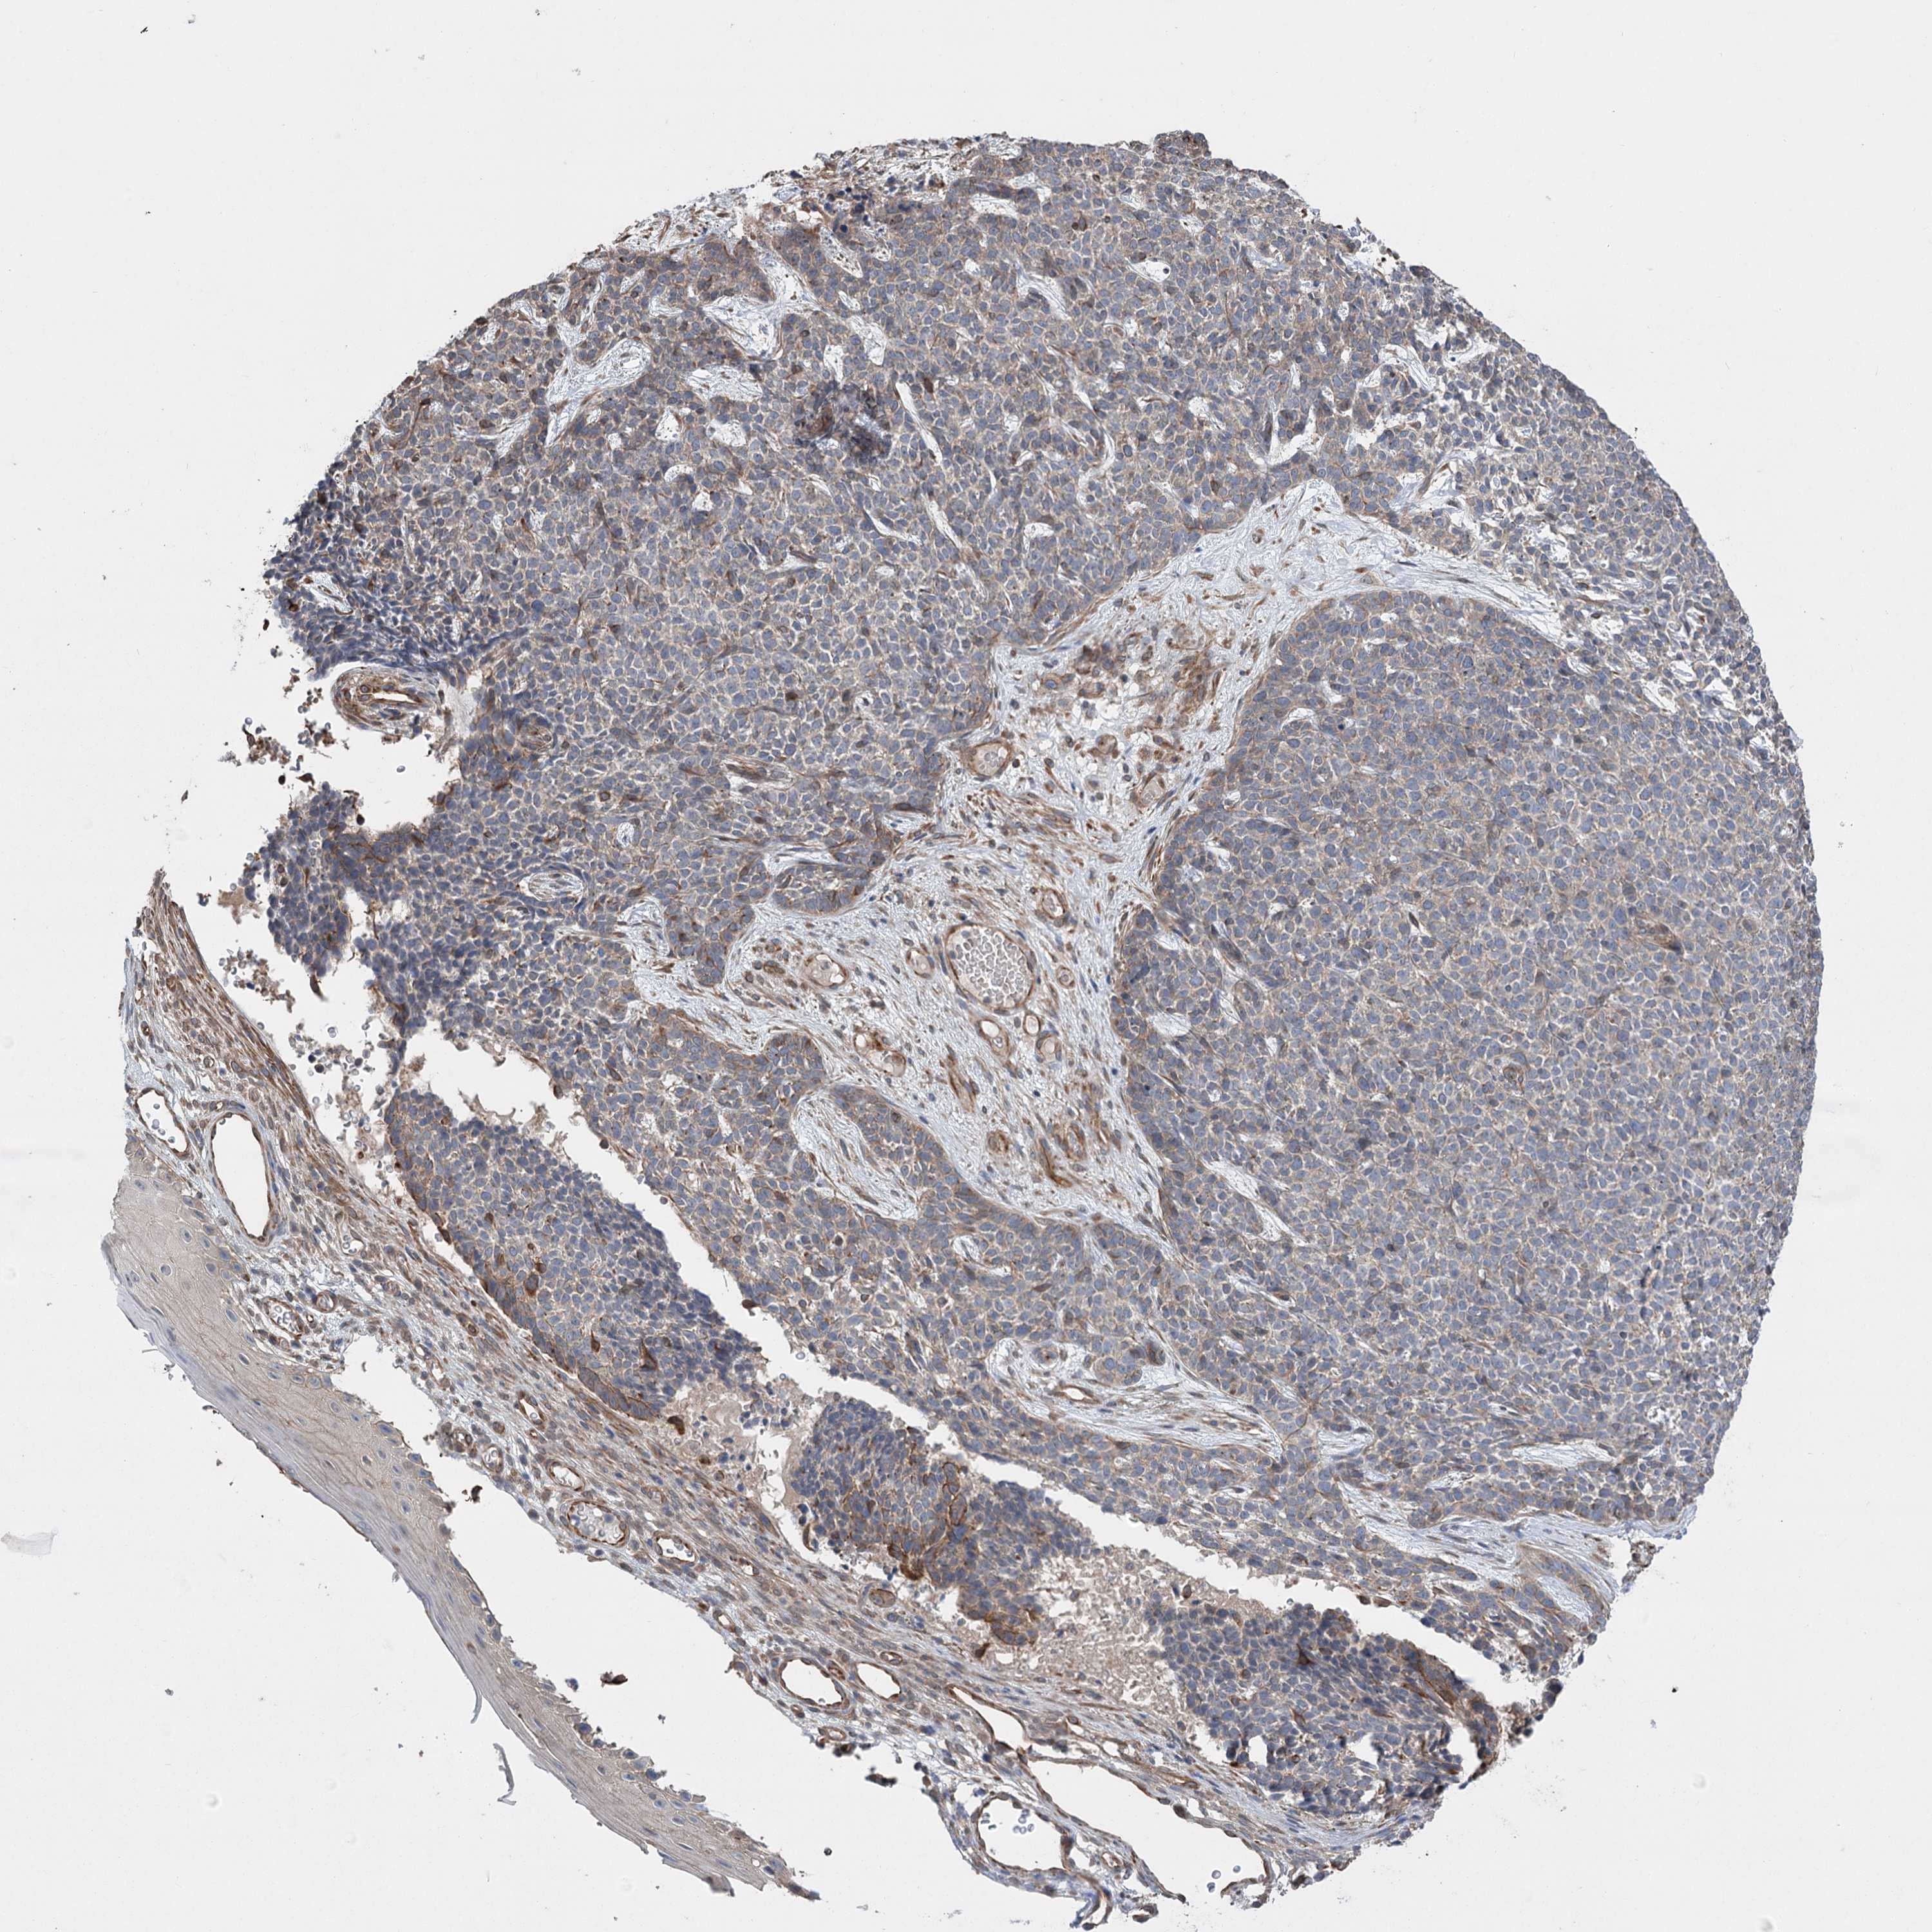

SKIN CANCER - Protein expressioni

A mouse-over function shows sample information and annotation data. Click on an image to view it in a full screen mode. Samples can be filtered based on level of antibody staining by selecting one or several of the following categories: high, medium, low and not detected. The assay and annotation is described here.

Antibody staining in the annotated cell types in the current human tissue is reported as not detected, low, medium, or high, based on conventional immunohistochemistry profiling in selected tissues. This score is based on the combination of the staining intensity and fraction of stained cells.

Each image is clickable and will lead to virtual microscopy that enables deeper exploration of all samples and also displays staining intensity scores, fraction scores and subcellular localization as well as patient and tissue information for each sample.

Antibody HPA036501

Staining

Medium

Strong

75%-25%

Cytoplasmic/membranous

Squamous cell carcinoma, metastatic, NOS